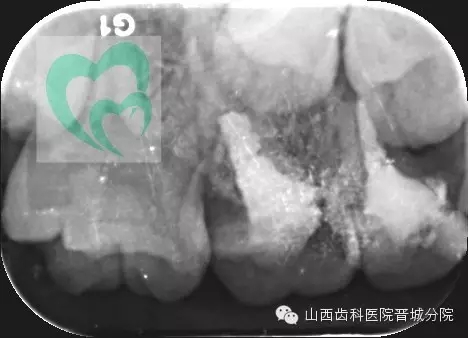

下面展示一例由我院龐超醫(yī)生操作并整理資料的兒童乳牙預成冠病例。

來源于山西齒科醫(yī)院